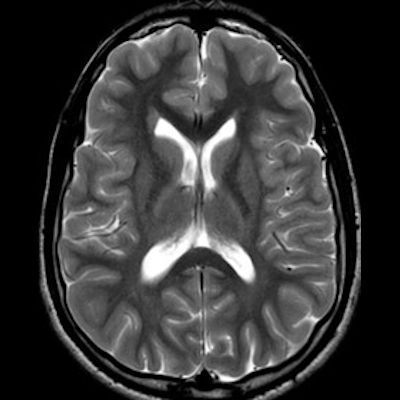

11 ay, Nöbet

Charlevoix-Saguenay Otozomal Resesif Spastik Ataksisi (ARSACS)

ARSACS (Charlevoix-Saguenay otozomal resesif spastik ataksisi) Sendromu